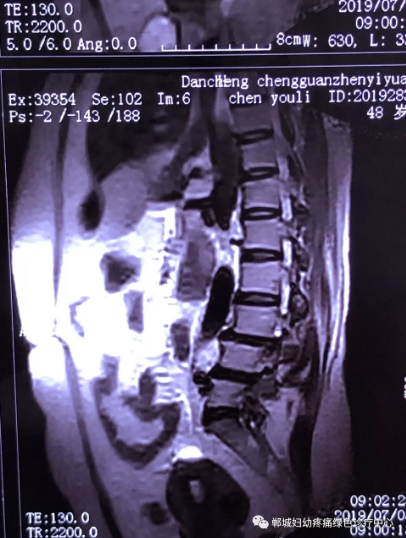

2年前,雙樓鄉(xiāng)的陳女士不小心摔了一跤后出現(xiàn)腰痛,當(dāng)時(shí)到藥店買(mǎi)了膏藥來(lái)貼,疼痛減輕了一些,但是從此以后反反復(fù)復(fù)出現(xiàn)腰痛。到處進(jìn)行治療,不見(jiàn)好轉(zhuǎn),最近腰痛加重了,痛得受不了,出現(xiàn)行走后甚至持續(xù)的雙下肢后側(cè)或后外側(cè)放射性的疼痛麻木、間歇性跛行等癥狀。陳女士趕忙去醫(yī)院治療,做了磁共振檢查后確診為腰椎滑脫、腰椎反弓。醫(yī)生都告訴她需要手術(shù)治療。隨后她又帶著片子咨詢了好幾家醫(yī)院,結(jié)果都是一樣,她已經(jīng)做好了手術(shù)的打算。

治療前

不經(jīng)意間聽(tīng)到有人說(shuō)醫(yī)院疼痛科可以不吃藥不打針,用無(wú)痛苦、無(wú)創(chuàng)傷的方法治療腰痛。陳女士就抱著試試看的心理來(lái)到了鄲城縣婦幼保健院疼痛科,疼痛科時(shí)慶祥主任詳細(xì)了解病情,結(jié)合腰椎磁共振及體征后告訴陳女士她不用手術(shù),通過(guò)腰椎脊柱定位周期減壓牽引系統(tǒng)(外星艙)也能解決腰痛、腰椎滑脫、腰椎反弓這些問(wèn)題。陳女士未曾想到經(jīng)過(guò)十五天的治療后腰部及下肢放射性疼痛癥狀基本消失。陳女士感到十分激動(dòng)與感謝,就在當(dāng)?shù)匦l(wèi)生院做了一個(gè)腰椎正側(cè)位x片和之前的片子作對(duì)比,發(fā)現(xiàn)腰椎滑脫明顯改善。她說(shuō)道:感謝鄲城縣婦幼保健院疼痛科的所有醫(yī)護(hù)人員、感謝外星艙脊柱減壓治好了我的腰痛,也感謝告訴我來(lái)這里的人,她的一句話,讓我省了好幾萬(wàn)元的手術(shù)費(fèi)!